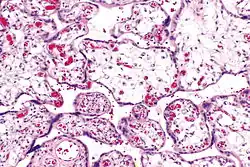

| Micrograph of villous immaturity. H&E stain. | |

Immature chorionic villi are larger and have more central blood vessels; thus, the diffusion distance for gas and nutrient exchange is larger and, therefore, placental function is impaired.

Low mag. -